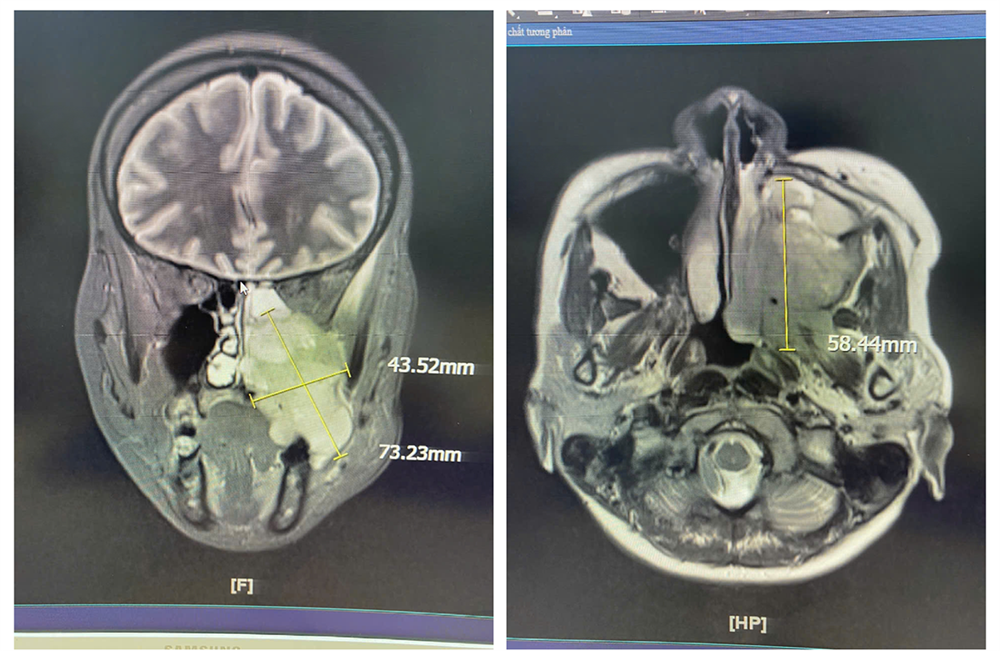

Các chẩn đoán hình ảnh bằng MRI, nội soi tai mũi họng cho thấy nữ bệnh nhân có khối u xuất phát từ xoang hàm - sàng trái, lan xuống khẩu cái, hố chân bướm hàm và vùng dưới thái dương trái. Kết quả sinh thiết mẫu mô từ hốc mũi và răng ghi nhận tổn thương phù hợp với Carcinoma tế bào gai không sừng hoá (ung thư).

ThS.BS.CKII Lê Nhật Vinh, Phụ trách khoa Liên chuyên khoa - Bệnh viện Đa khoa Quốc tế Nam Sài Gòn cho biết, khối u không còn nằm giới hạn trong xoang mũi, mà đã lan sâu đến nhiều khu vực giải phẫu quan trọng như khẩu cái (trần miệng), vùng sàn sọ và hố chân bướm hàm.

Theo các bác sĩ, so với những trường hợp ung thư vùng đầu - mặt - cổ thường gặp khác như ung thư khoang miệng hay thanh quản (dễ tiếp cận, phát hiện sớm), trường hợp của nữ bệnh nhân này phức tạp hơn, do khối u nằm sâu trong xoang hàm - xoang sàng, lan rộng đến các khoang khó tiếp cận như hố chân bướm hàm, vùng dưới thái dương, sàn sọ - nơi có nhiều mạch máu và dây thần kinh lớn.